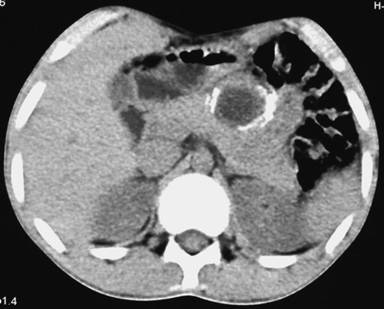

Plain X-ray of the abdomen revealed classical curvilinear calcification in only one patient with a hydatid cyst in the pancreatic body (Figure 1). Ultrasonographic examination which recorded the site, size and extent of the lesions, documented the cystic lesions as anechoic rounded structures in all cases. An abdominal CT scan documented the cysts as spherical hypodense space-occupying lesions. All the lesions were solitary, measuring 26-50 mm in diameter (mean 36.7 mm). Five lesions were cystic with thin walls and one lesion appeared as a multiseptated cyst. Magnetic resonance imaging for defining the lesion and its relationship with the pancreatic duct was performed in three patients (two lesions in the head and one in the body of the pancreas). Two lesions were located in the head (Figure 2, 3, 4, 5), two in the body (Figures 6 and 7) and two in the tail region of the pancreas (Figure 8). In two cases, a preoperative diagnosis was possible due to the presence of classical features which also included a concomitant hydatid cyst in the liver in one patient. All patients underwent surgical exploration; intraoperative cyst puncture for aspiration cytology was successful in three cases (two cases with cysts in the head and one case with a cyst in the body of the pancreas); the results of cytological examination were positive in all cases. A fragmented laminated membrane was observed in two patients, scoliosis in three and hooklets in one patient (Figure 9). The laminated membrane was seen as a foliated, acellular, pale, eosinophilic structure which stained strongly positive with periodic acid Schiff staining and negative with alcyan blue staining. The hooklets had a characteristic shape presenting as a blade, a guard and a root. They were not stained with Papanicolaou stains and their appearance was enhanced by turning down the microscope condenser. There were no complications after diagnostic aspiration. In all three cases, the aspirated fluid was colorless and contained a mean sodium level of 128 mEq/L (range: 128-130 mEq/L), chloride level of 69 mEq/L (range: 65-70 mEq/L) and potassium level of 5.8 mEq/L (range: 5.4-6.3 mEq/L). Cysts in the distal pancreas observed in the two patients were treated by a distal pancreatectomy with splenectomy. Cysts in the body were treated by a pericystectomy in one patient (Figure 10) and a central pancreatectomy in another patient. Cysts in the head region in two patients were treated with evacuation, partial cystectomy and tube drainage of the cavity after protecting the surgical area with a scolicidal solution (Figure 11). Both patients underwent T-tube drainage of the common bile duct; there was rapid regression of the jaundice in these patients. The T-tube cholangiogram confirmed the free flow of bile into the duodenum; the tubes were eventually removed in the third postoperative week. Postoperative confirmation of the hydatid cysts was obtained on the basis of the histopathological findings. There were no postoperative complications; all patients recovered uneventfully. The antihelminthic drug, albendazole, was administered postoperatively (10 mg/kg body weight/day) in all cases for a period of 6 months. All the patients were followed up at three-month intervals and each patient underwent clinical examination, abdominal ultrasonography and indirect hemagglutination tests; no patient had cyst recurrence or dissemination. The mean follow-up time was 58.7 months (range: 4-120 months).

Figure 6. Contrast-enhanced computed tomography scan demonstrating a solitary cystic lesion (33 mm) in the body of the pancreas with internal daughter cysts (Patient #3). |